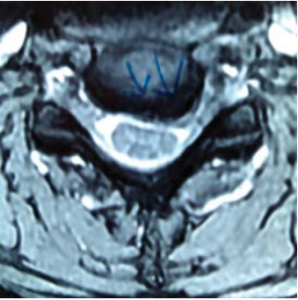

MRI showed severe prolapsed cervical disc indenting the spinal cord and neuroforamen’s of C5/6. There was evidence of spinal cord pressure with T2 changes seen on the sagittal views.